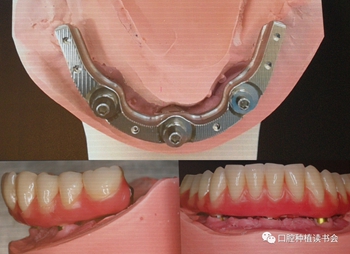

周國輝教授的演講題目是《Trefoil-無牙頜種植新理念》,Trefoil是用于下頜無牙頜的種植修復(fù)新概念(圖5),Trefoil修復(fù)體是固定修復(fù)體;它與All-on-4 不同的地方是它使用3顆直立的軟組織水平植體,種植位點位于雙側(cè)刻孔之間,采用預(yù)成支架與樹脂義齒結(jié)合的方式實現(xiàn)即刻負重,預(yù)成支架與基臺的連接可以補償植體之間的誤差,達到被動就位,6小時完成修復(fù)。手術(shù)當(dāng)天戴入正式修復(fù)體,進一步簡化了手術(shù),減少了費用,預(yù)成支架是成品,避免臨時修復(fù),節(jié)約時間,減少復(fù)診次數(shù),對于年齡大的患者更有意義。

圖5 采用Trefoil理念的下頜無牙頜方案

技師在模型上完成預(yù)成支架+樹脂義齒的制作,戴入口內(nèi)完成即刻負重,手術(shù)后兩個月觀察種植體軟硬組織整合良好(圖9、10)。

圖9 手術(shù)當(dāng)天制作的正式修復(fù)體